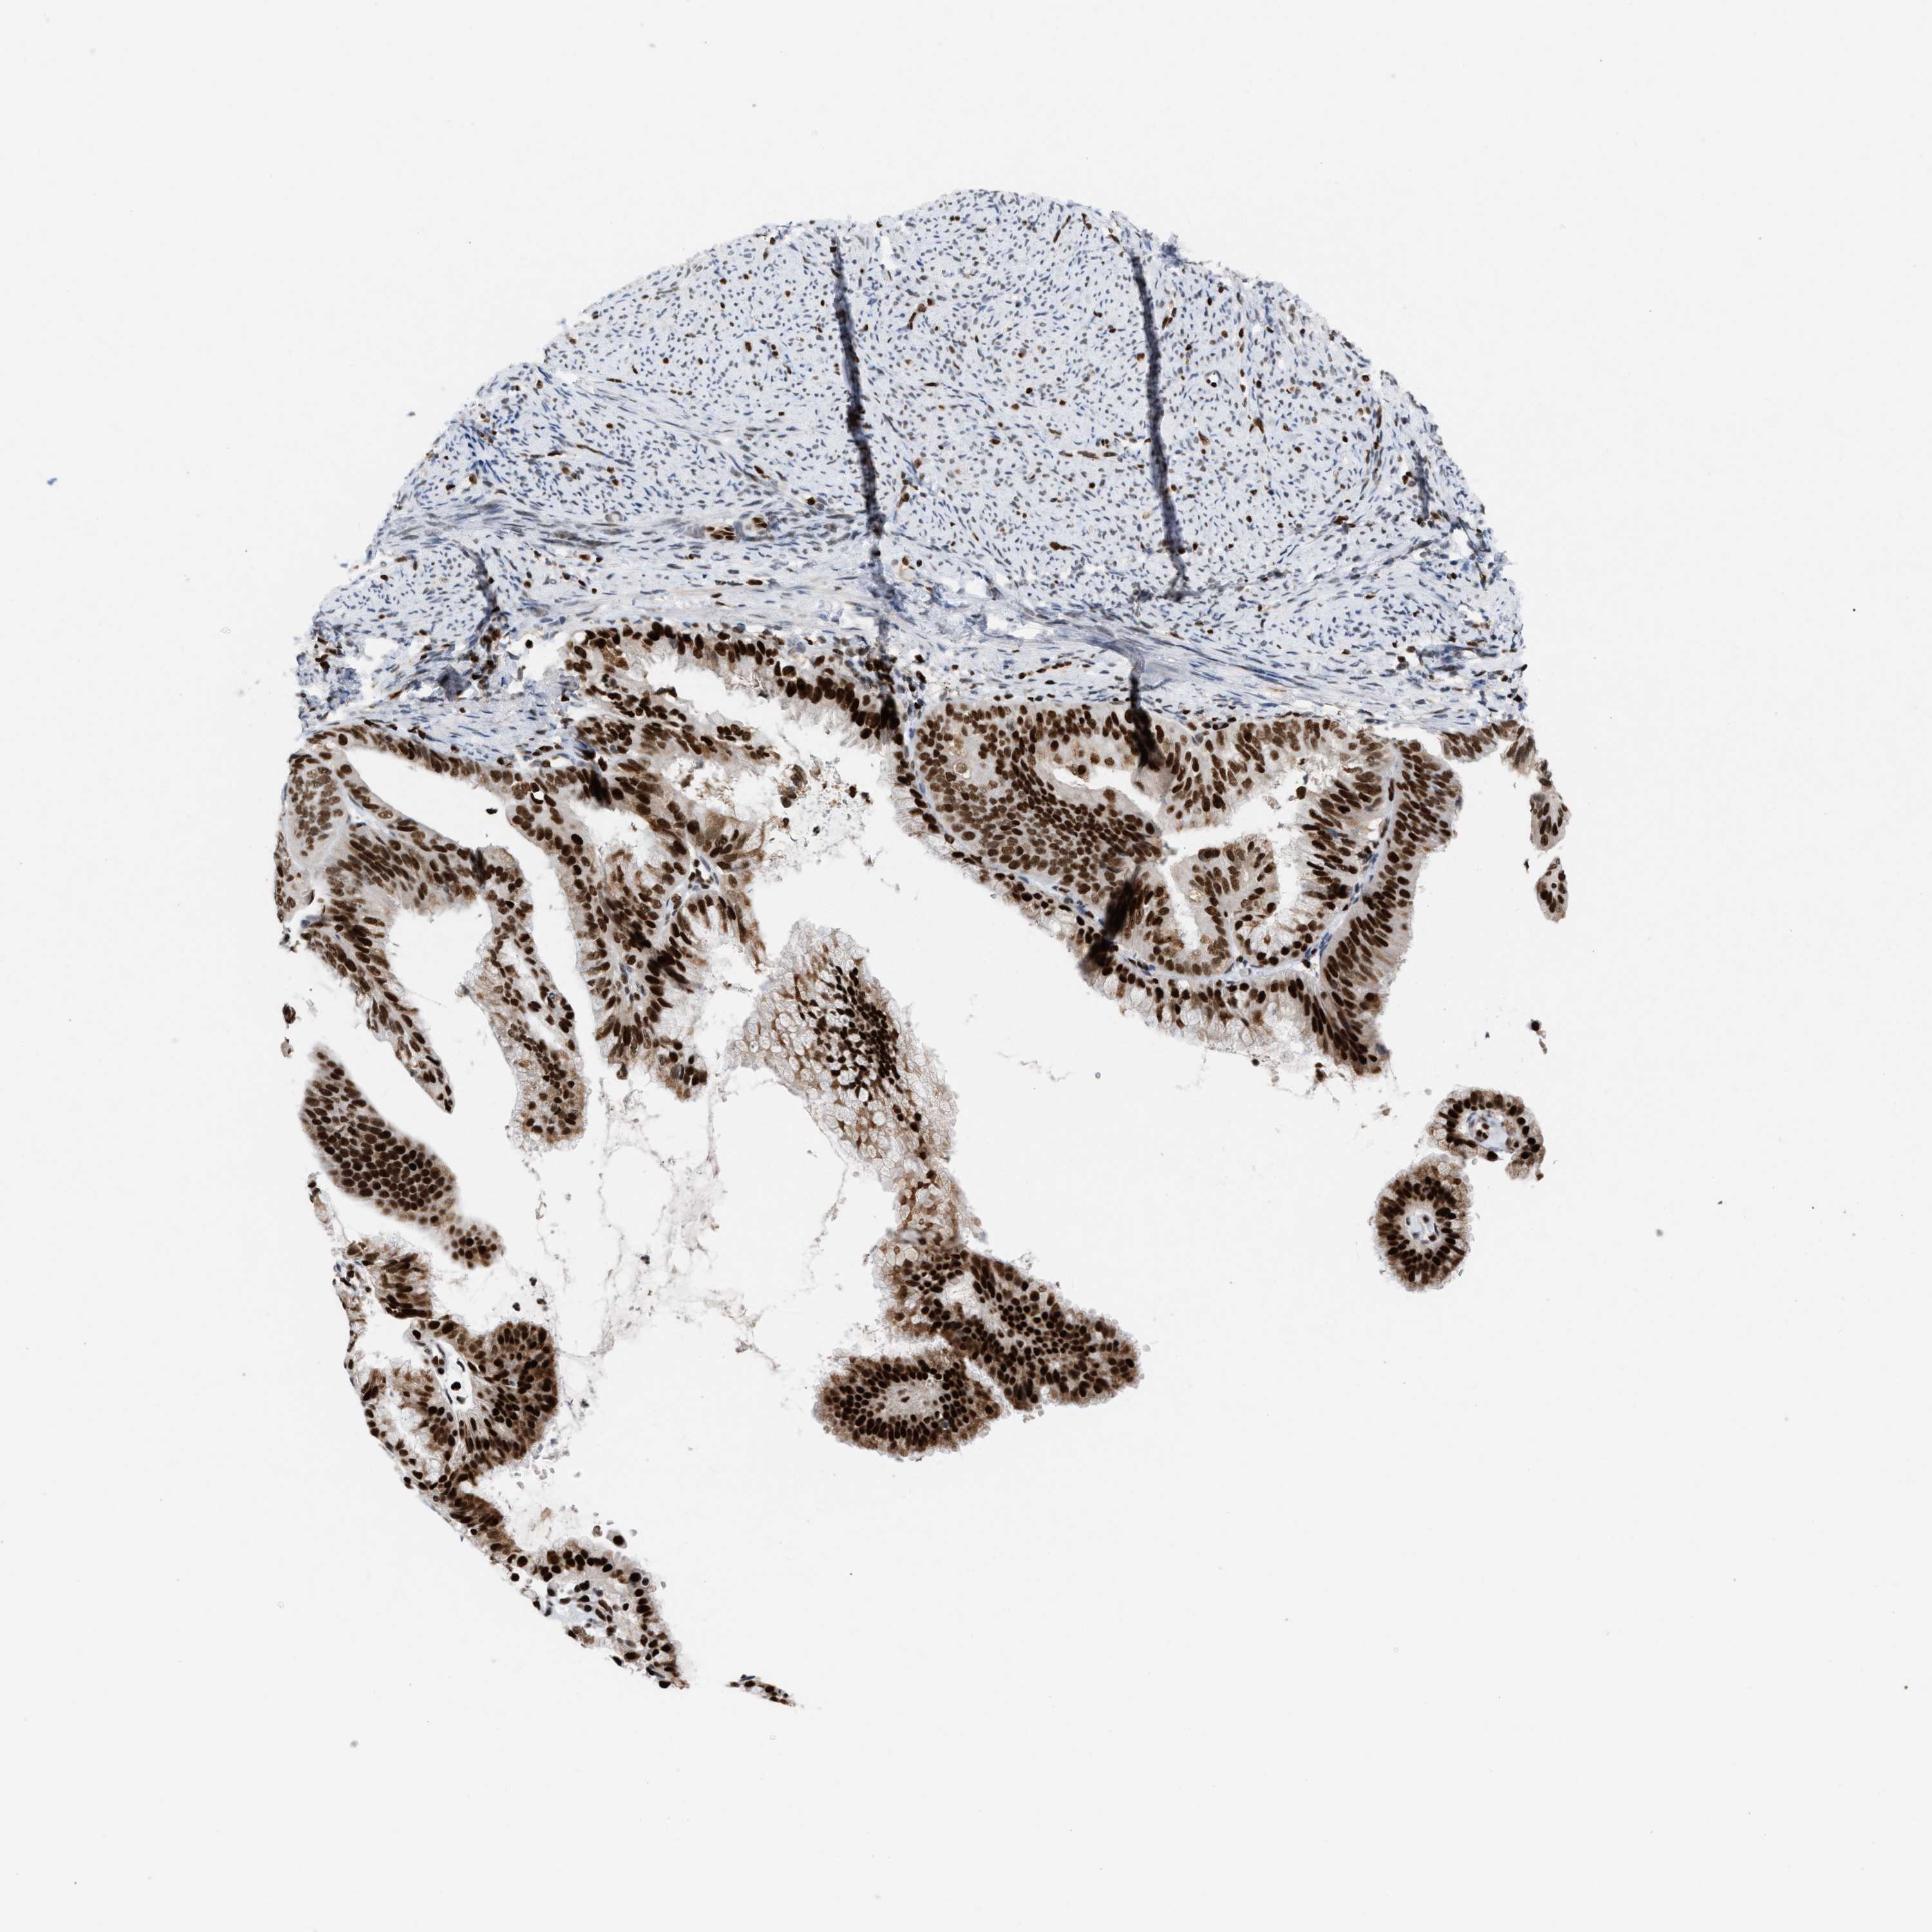

ENDOMETRIAL CANCER - Protein expressioni

A mouse-over function shows sample information and annotation data. Click on an image to view it in a full screen mode. Samples can be filtered based on level of antibody staining by selecting one or several of the following categories: high, medium, low and not detected. The assay and annotation is described here.

Note that samples used for immunohistochemistry by the Human Protein Atlas do not correspond to samples in the TCGA dataset.

Antibody stainingi

Antibody staining in the annotated cell types in the current human tissue is reported as not detected, low, medium, or high, based on conventional immunohistochemistry profiling in selected tissues. This score is based on the combination of the staining intensity and fraction of stained cells.

Each image is clickable and will lead to virtual microscopy that enables deeper exploration of all samples and also displays staining intensity scores, fraction scores and subcellular localization as well as patient and tissue information for each sample.

Antibody HPA022961

Antibody HPA024457

Staining

High

Medium

Low

Not detected

Intensity

Strong

Moderate

Weak

Negative

Quantity

>75%

75%-25%

<25%

None

Location

Nuclear

Cytoplasmic/membranous

Cytoplasmic/membranous,nuclear

Adenocarcinoma, NOS

Adenoma, NOS